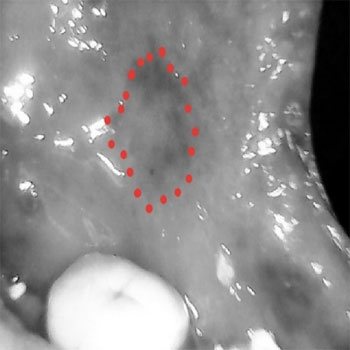

The narrow and mini head of the device can be inserted in to the oral cavity even in restricted mouth opening conditions such as OSMF and Squamous cell carcinomas to allow better visualization even in hidden areas of the oral cavity.

Lesion in Retro molar region with other oral cancer screening devices with larger head and extra oral imaging

The HD camera with 5MP will enables visualizations more clearly

Image of the lesion after filtering with smaller head and camera in the device after filtering.

same lesion with the camera in the device with low intensity of light